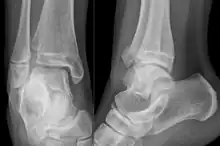

| X-ray of a Tillaux fracture in an 11 year old female | |

A Tillaux fracture is a Salter–Harris type III fracture through the anterolateral aspect of the distal tibial epiphysis.[1] It occurs in older adolescents between the ages of 12 and 15 when the medial epiphysis had closed but before the lateral side has done so,[2] due to an avulsion of the anterior inferior tibiofibular ligament, at the opposite end to a Wagstaffe-Le Fort avulsion fracture

If the displacement at fracture is less than 2 mm, it may be managed conservatively. However, displacement requires open reduction and internal fixation, especially when displacement is over 2 mm.[4]